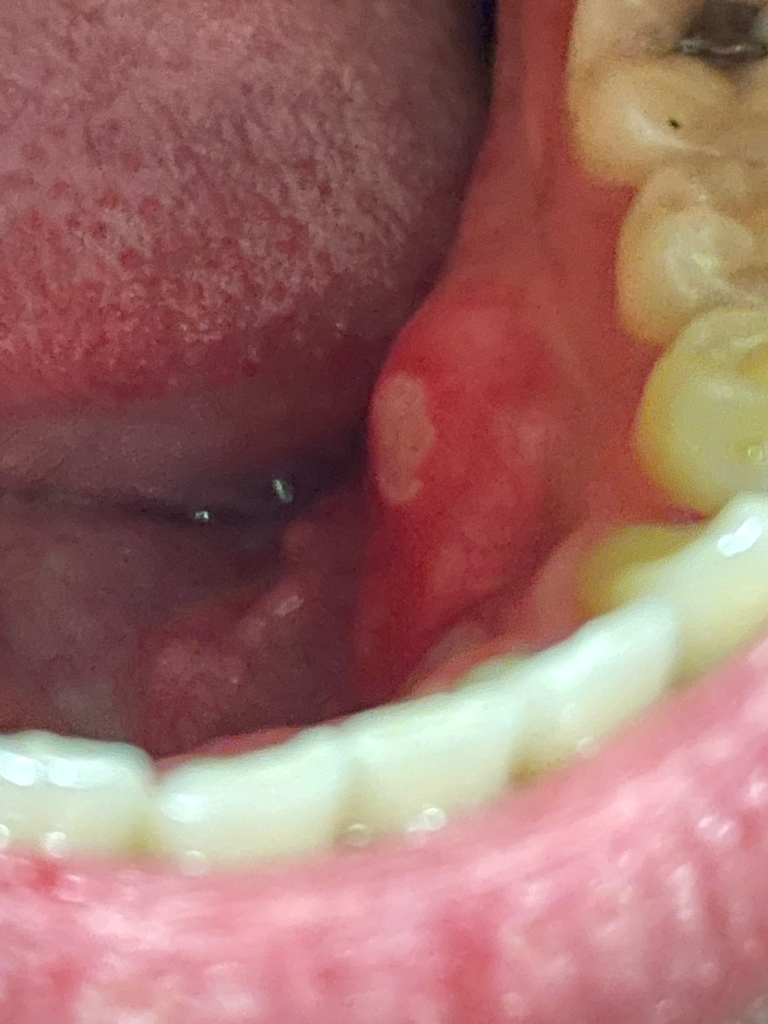

매독성 구내염은 매독이 원인인 구내염으로, 입술이나 잇몸에 타원형의 구진이 생기는 것이 특징입니다. 매독성 구내염은 통증이 거의 없고, 2~3주 정도 지나면 자연적으로 치유됩니다. 사진으로만으로는 매독성 구내염인지 여부를 정확히 알 수 없습니다. 만약 매독성 구내염이 의심된다면 병원에서 검사를 받아보는 것이 좋습니다. 매독은 성관계를 통해 전염되는 질환으로, 성관계를 한 적이 있다면 매독 검사를 받아보는 것이 좋습니다. 매독은 초기에 치료하면 완치가 가능하지만, 치료하지 않으면 심각한 합병증을 유발할 수 있습니다.